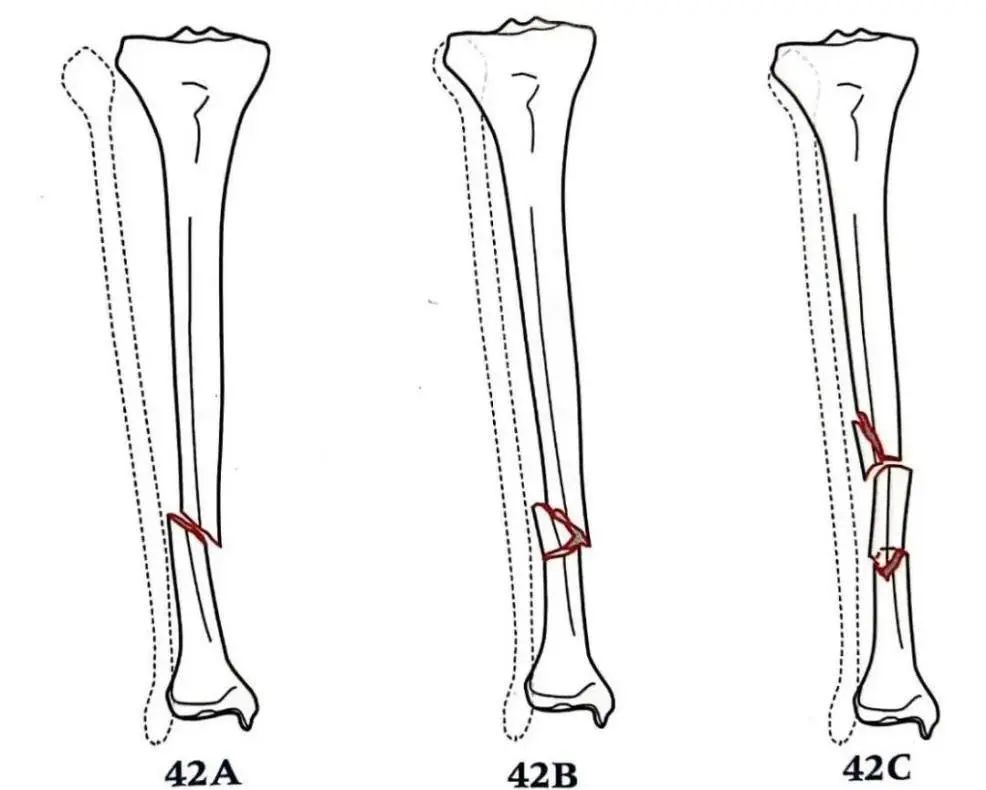

AO/OTA骨折脫位分型(xing):

AO / OTA骨(gu)(gu)折脫位的(de)阿拉伯(bo)數字分(fen)型(xing)將脛骨(gu)(gu)干骨(gu)(gu)折設定為(wei)4(脛骨(gu)(gu))2(骨(gu)(gu)干)。A型(xing)對(dui)應(ying)有(you)一條骨(gu)(gu)折線(xian)的(de)簡(jian)單骨(gu)(gu)折。這是(shi)最(zui)常見的(de)類型(xing)。B型(xing)骨(gu)(gu)折有(you)個(ge)中間楔形骨(gu)(gu)折塊。C型(xing)骨(gu)(gu)折是(shi)由高能量損傷引起的(de),為(wei)粉碎性節段性骨(gu)(gu)折。

- 脛骨(gu)(gu)(gu)干簡單骨(gu)(gu)(gu)折或(huo)粉碎(sui)性骨(gu)(gu)(gu)折(AO 42A-C)

- 脛骨干(gan)多段性骨折(zhe)(AO 42C)